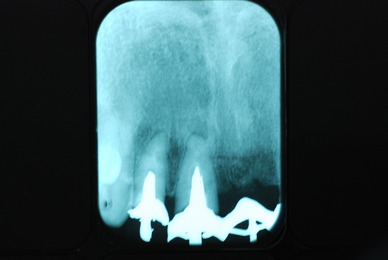

必ずばい菌が侵入しないようにしてばい菌である虫歯を除去します。

銀歯の下はばい菌だらけです。こういうのはよくあります。取り残しですね。![treatment_05[1]](https://livedoor.blogimg.jp/netdental/imgs/3/a/3ad019d0-s.jpg)